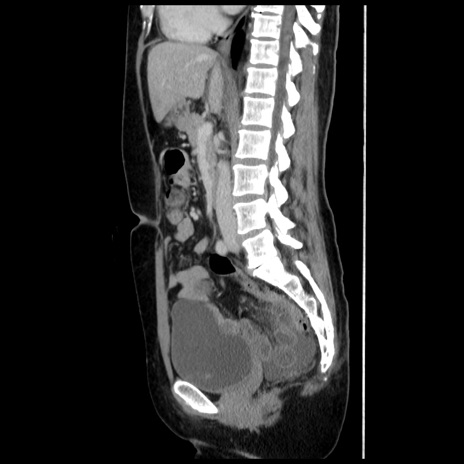

横断像

【症例】 50歳代女性

【主訴】 腹痛

【現病歴】前日生レバーを食べた。今朝に排便あり。 昼前に突然発症の腹痛を生じ、当院救急外来を受診した。

【既往歴】 子宮筋腫にてで子宮全摘後

【身体所見】 意識清明、腹部:平坦、軟、下腹部やや左を中心に圧痛・反跳痛あり、筋性防御あり

【データ】WBC 7800、CRP 0.07